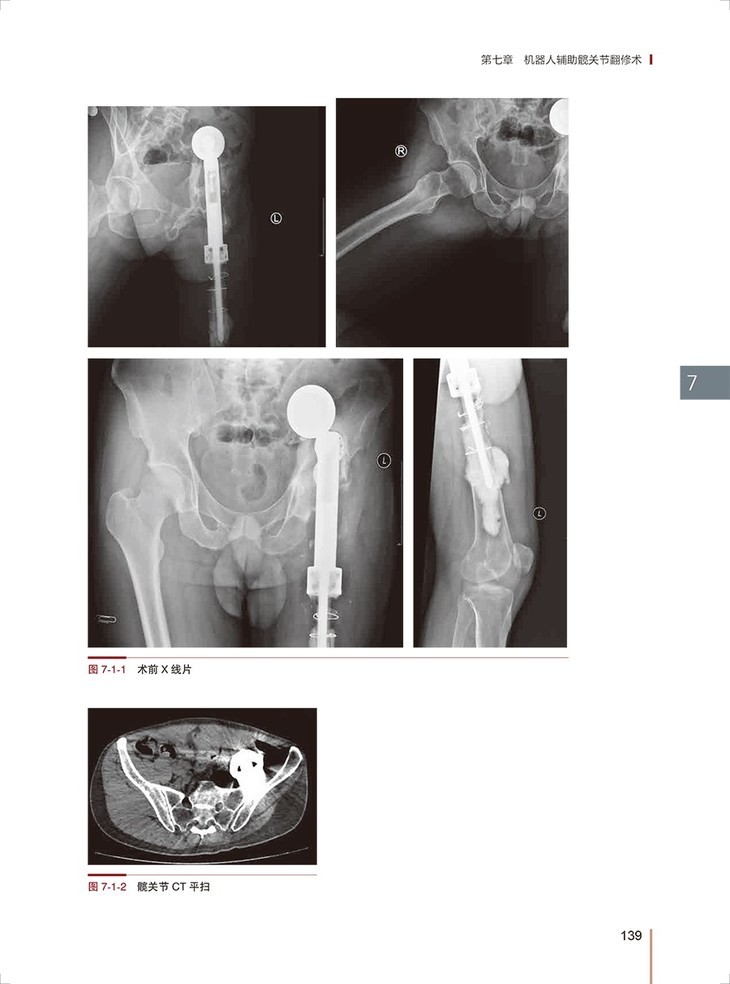

第七章 机器人辅助髋关节翻修术/ 135